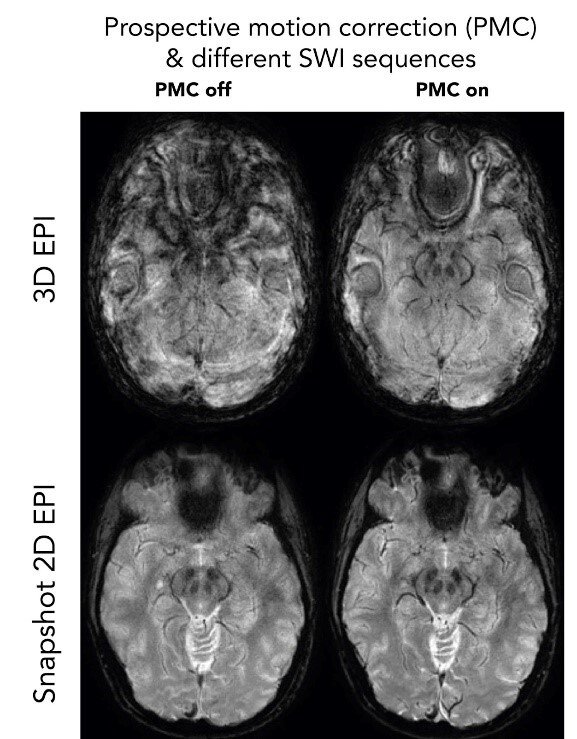

Motion robust pulse sequences - Snapshot SWI-EPI

Despite real-time motion correction with Tracoline or WRAD, it is fundamentally difficult to obtain good image quality with long-TE 3D sequences such as SWI. Even with an ideal motion correction, the phase changes in the brain (which occur due to long echo times) result in image artifacts (top-right, 3D EPI). With our snapshot 2D SWI EPI, a complete image plane is obtained in 0.1 s under the same phase conditions in the brain. Several repetitions of the same image plane are averaged after motion correction to increase the SNR to the appropriate level.